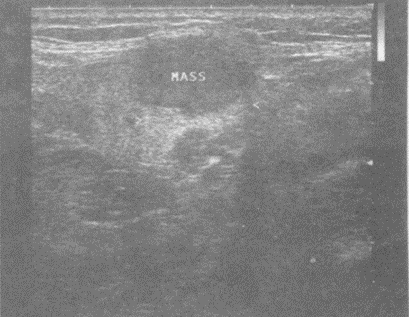

患者上肢可扪及一包块,质软、活动度差,加压可变形。如图,提示为()。

A.脂肪瘤